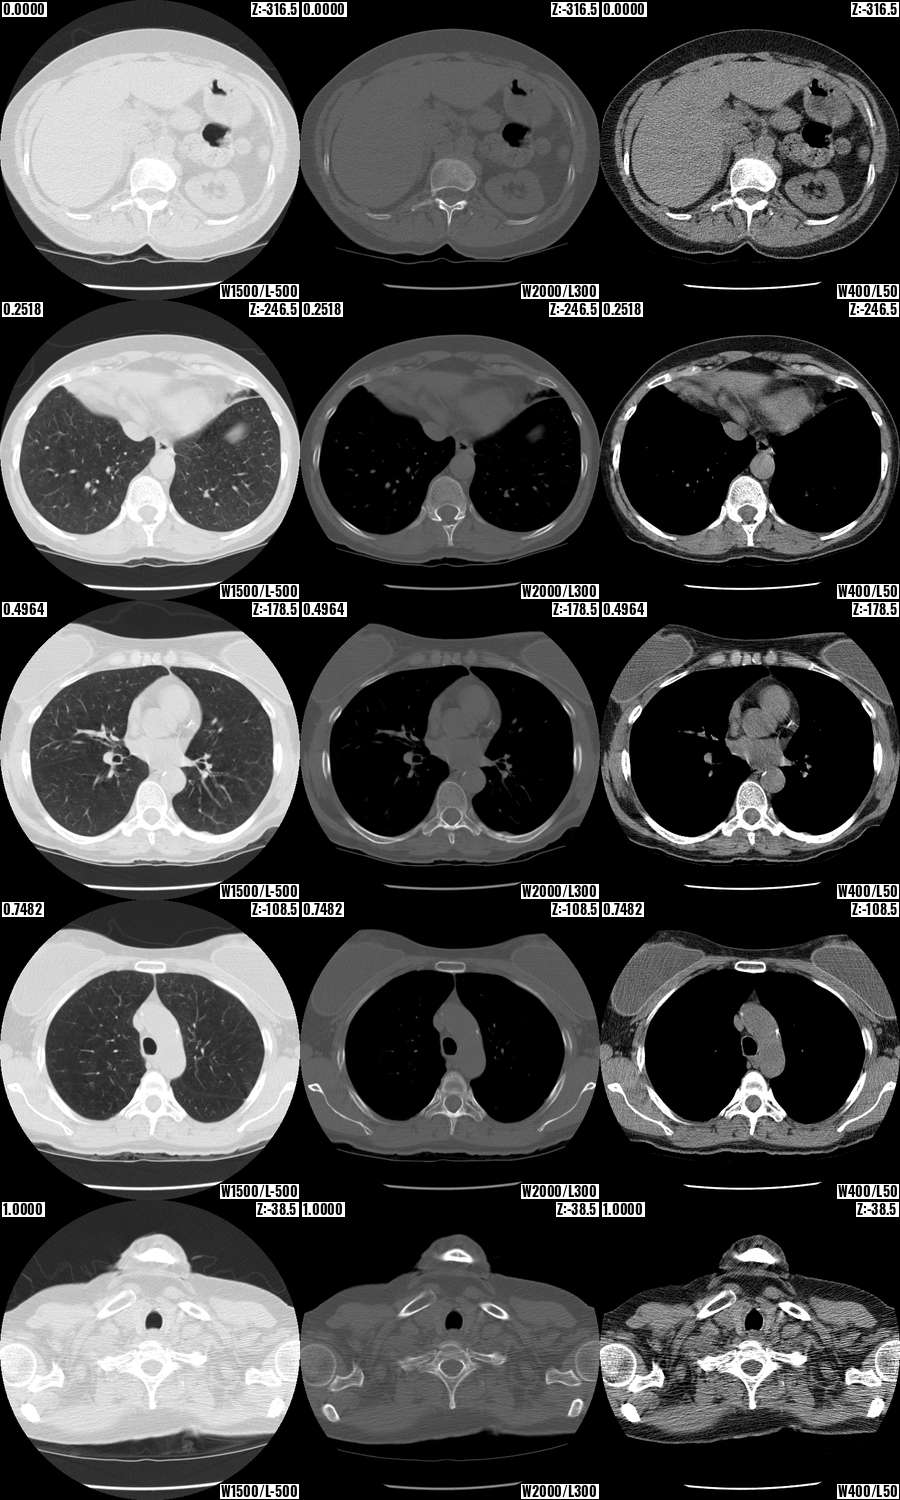

Contrast Mosaic: